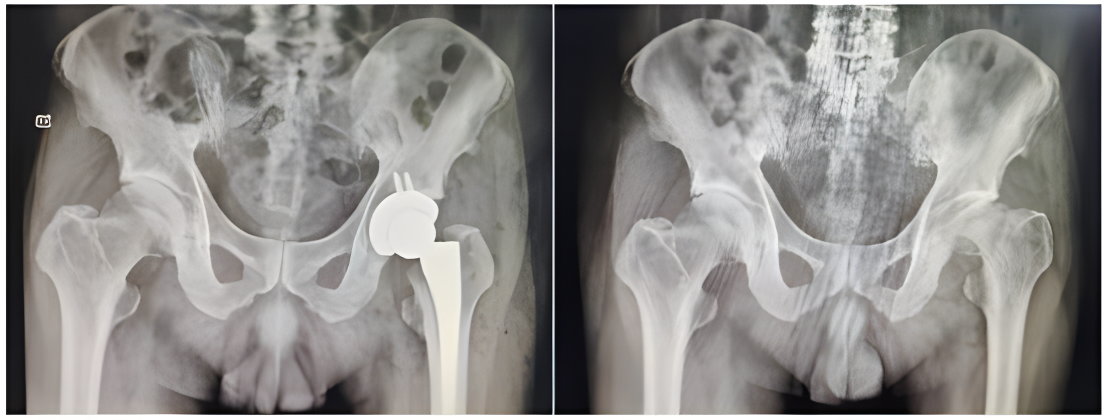

股骨头坏死手术前后X光片对比

发育性髋关节发育不良手术前后X光片对比